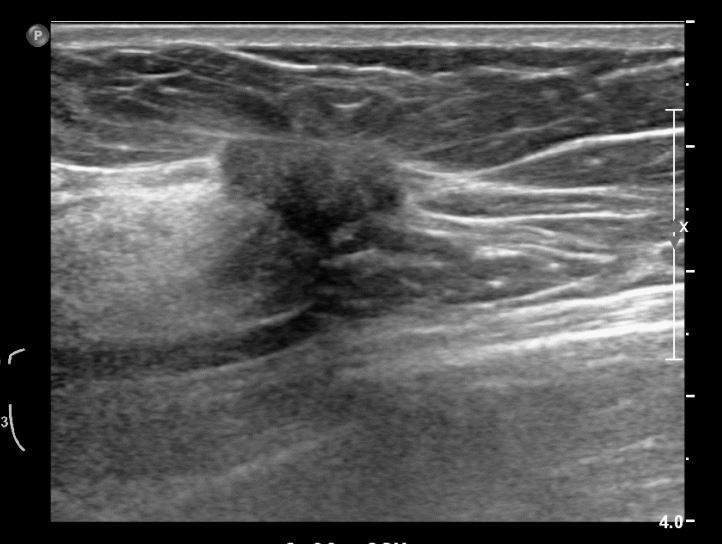

상기환자 외부검사상 이상소견으로 내원하신 50대 후반 여성분으로 우측 조직검사 시행해 침윤성 유방암으로 진단되었습니다